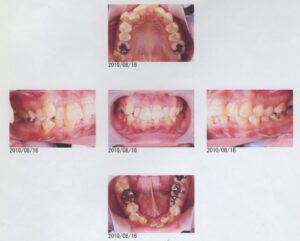

患者さんは14歳の中学2年性。臼歯部の虫歯治療で来院されました。

口腔内は、上下顎ともにごく僅かに叢生がありますが、臼歯部も1歯対2歯でちゃんと噛み合っていますし、

垂直被蓋、水平被蓋ともに正常であり、噛み合わせには特に問題があるようには思えません。

当然、咀嚼に問題はないのですが、食事中に時々口の中から物が溢れてしまうことがあるというのです。

よく観察してみるとリラックスした状態では口唇が完全に閉鎖しきれず、上前歯が口元から少し見えています。

口元が閉じた状態では明らかに口輪筋とオトガイ筋が緊張しており、側方からみると口元が少し出っ張っている感じです。

この患者さんは、主に上顎が優勢であり、上下歯列は理想的な位置より前に出てきてしまっています。